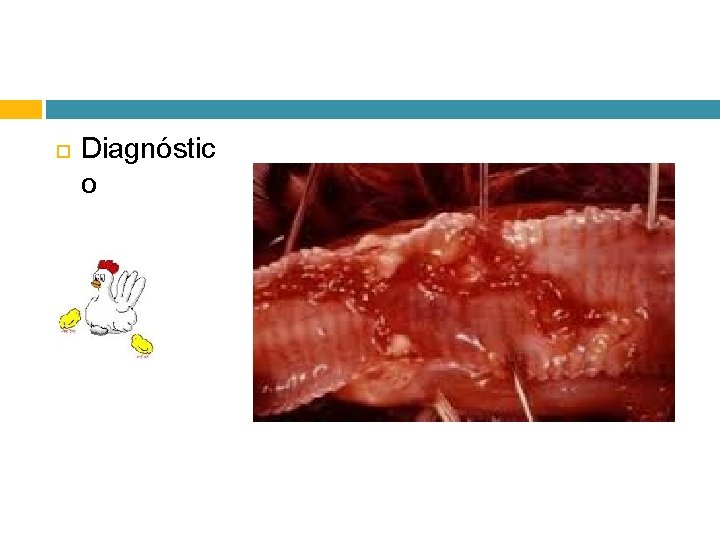

Diagnóstic o